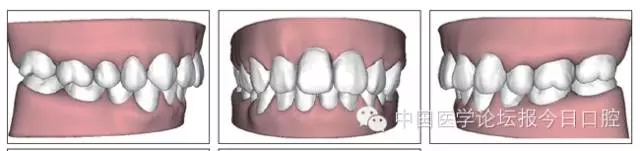

圖2 治療前口內(nèi)像

圖9 治療后口內(nèi)像

圖11 治療后ODS模型

圖12 保持半年后口內(nèi)像